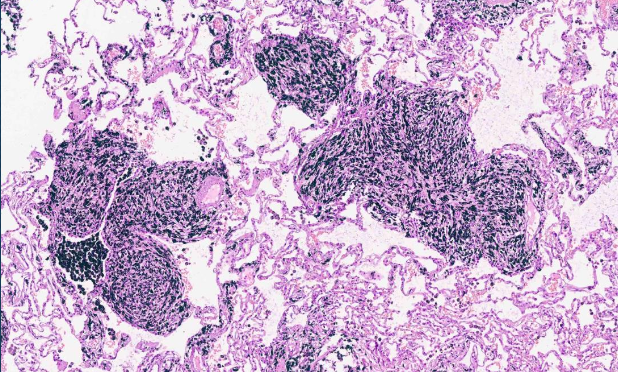

¿Qué es?

Bronquiectasias